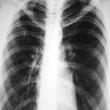

Skin tests, blood tests, x-rays, and other tests can tell if you have TB. If not treated properly, TB can be deadly. You can usually cure active TB by taking several medicines for a long period of time.